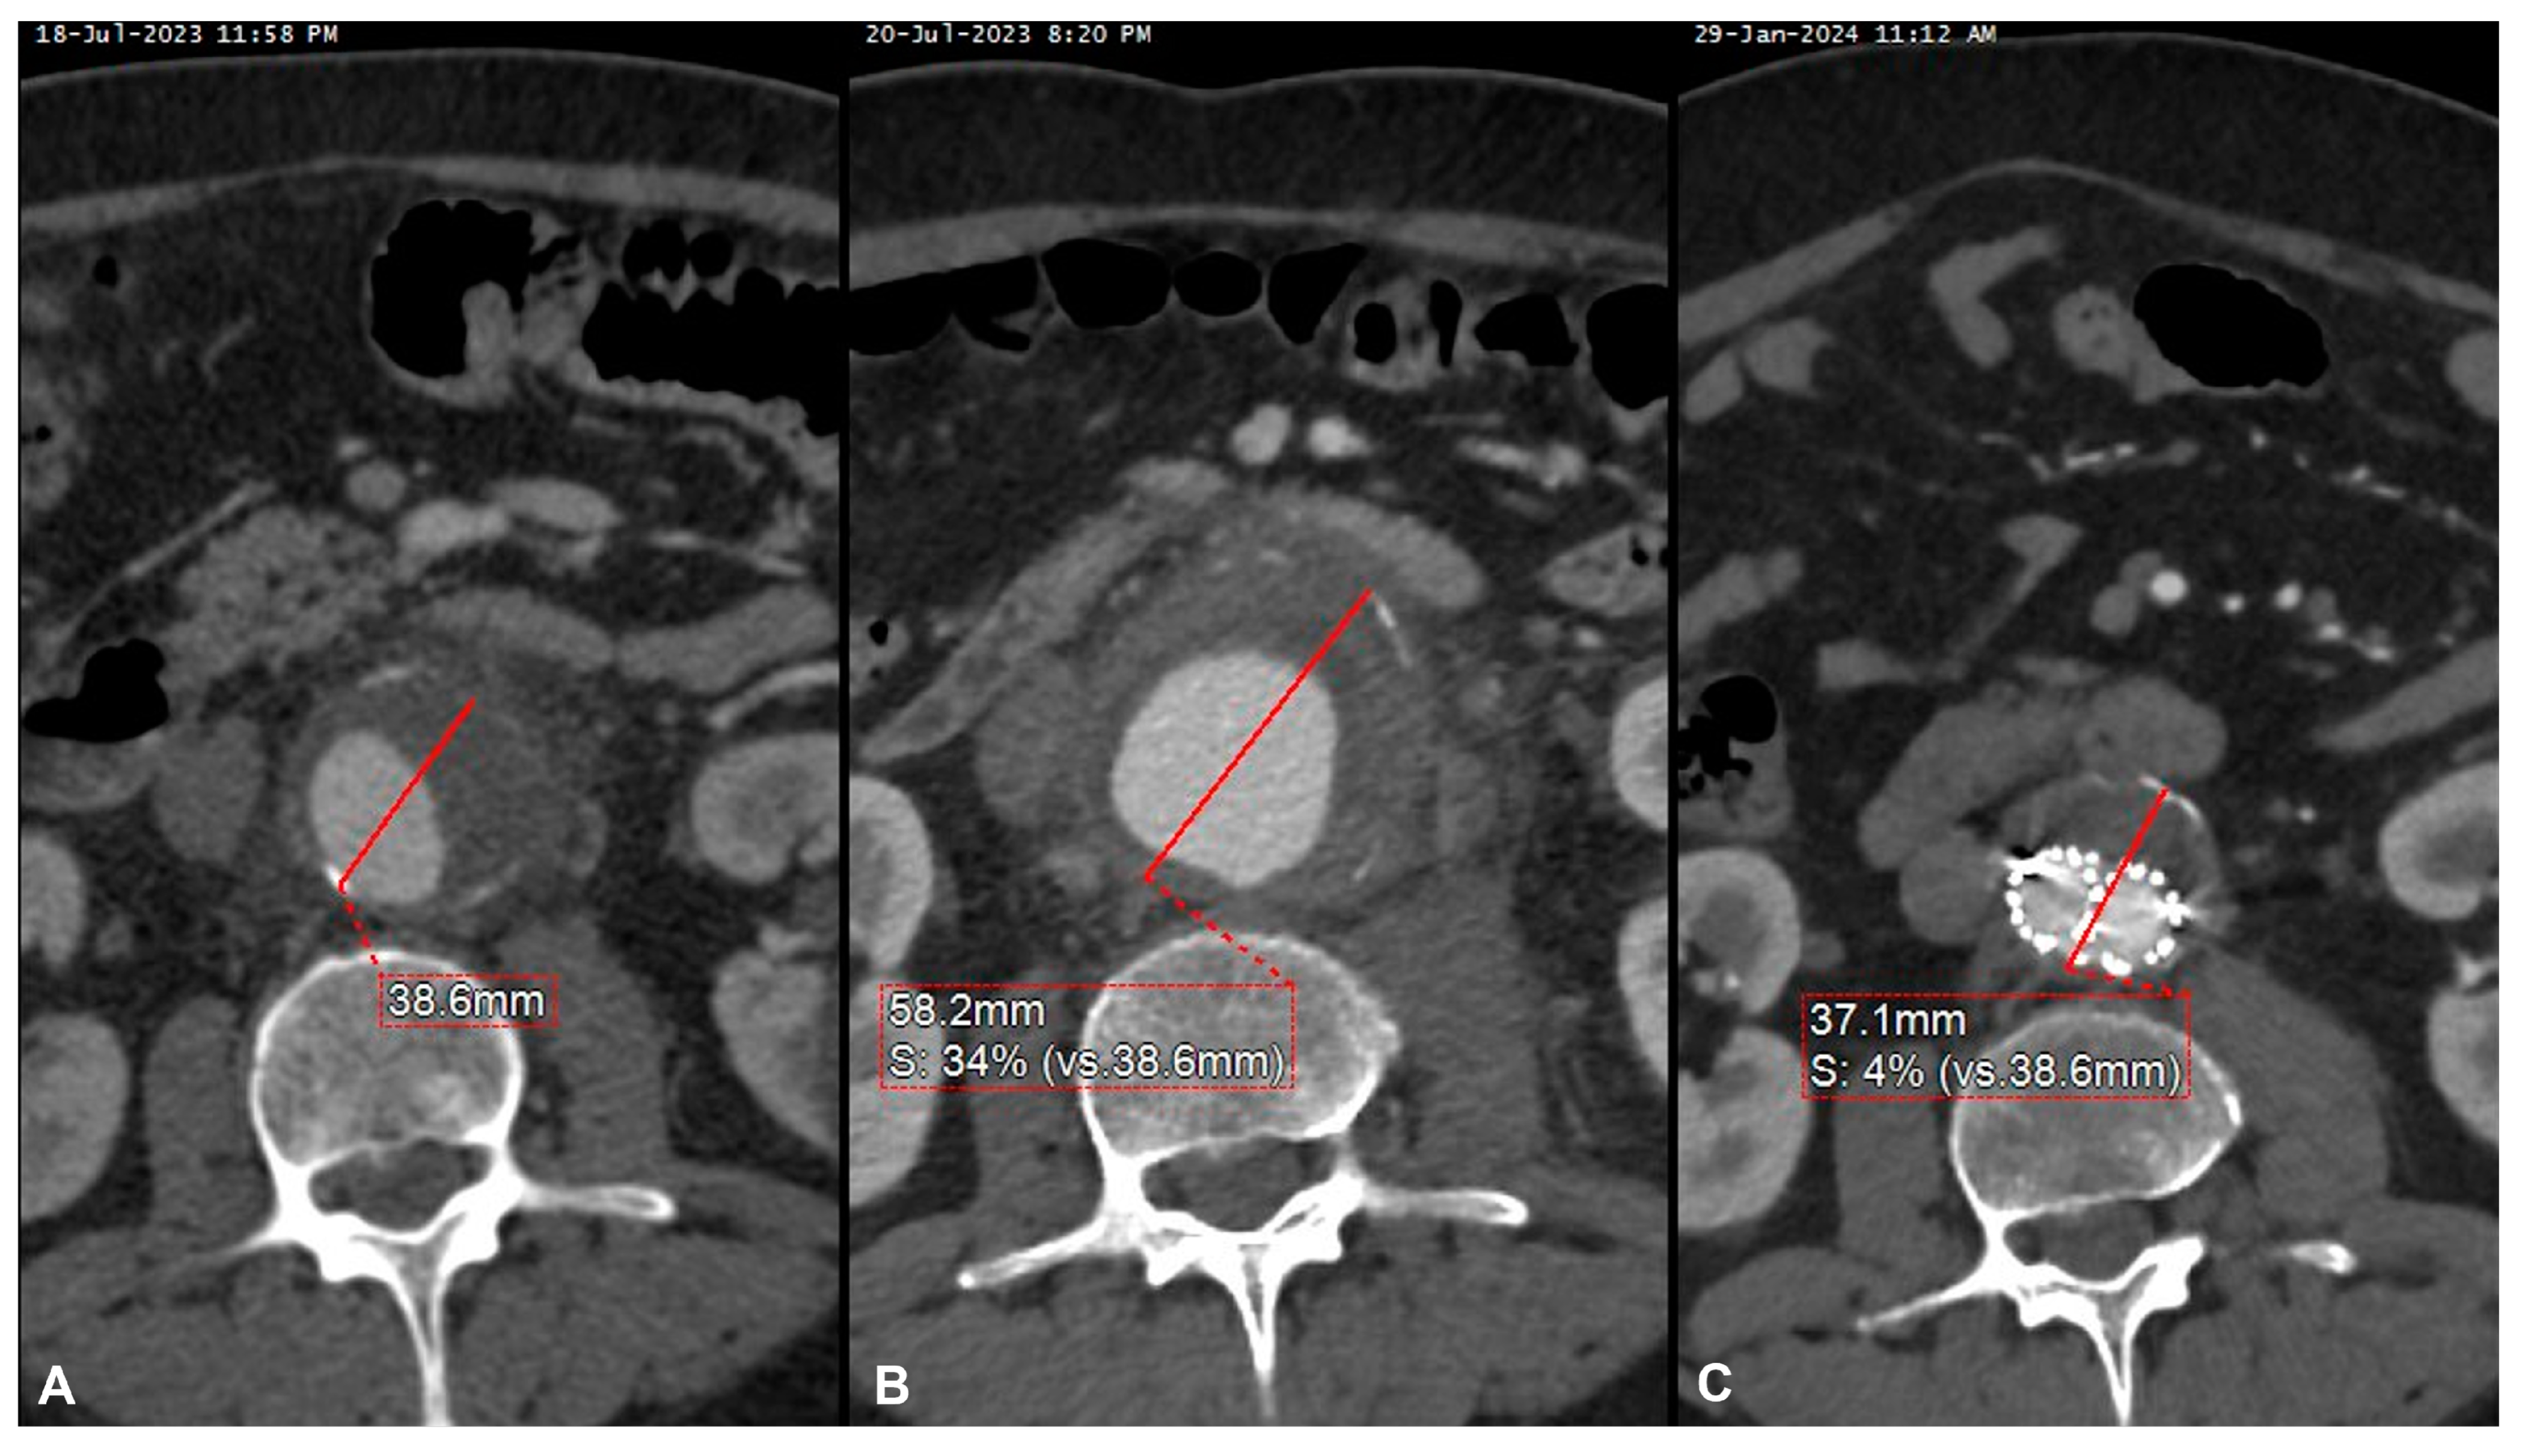

| 9 | M | 69 | Sepsis in pre-existing AAA | Salmonella spp. Non-Typhi | Yes | Symptomatic rapidly growing AAA | Cotrimoxazol | EVAR | Alive | 7 | Increase in wall thickening | - |